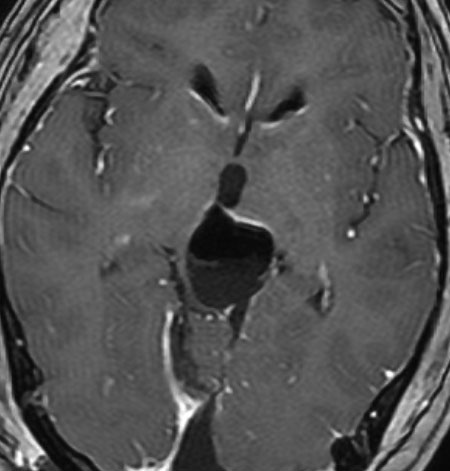

左はT1強調画像,右はFLAIR画像です。中脳視蓋が腫れて腫瘍がにじむように広がっているのがわかります。この腫瘍本体は15歳の時から21歳の時まで大きくなっていないので,中脳視蓋グリオーマ tectal gliomaの診断です。

T1強調ガドリニウム増強画像です。15歳の時は腫瘍の半分以上が強くガドリニウム増強されていましたが,この21歳の時の画像では,中心部やや右寄りに増強像が認められるだけです。この性質は,腫瘍が毛様細胞性星細胞腫であることを示しています。